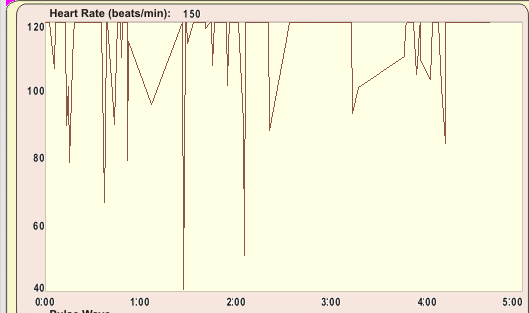

自律神経バランスを測定した結果

Hさんの自律神経バランスを測定したところ、副交感神経の働きが低下し、 自律神経全体がアンバランスな状態でした。 副交感神経がうまく働かないと、身体は常に緊張状態になります。 結果として「回復力が落ち」「痛みを感じやすい脳の状態」になってしまうのです。 つまり、トレイルランニングそのものが原因ではなく、ストレスによって痛みに敏感になっていたのです。

上記の測定結果は、現在は、TAS9VIEWという新しい自律神経バランス測定器での計測になっています